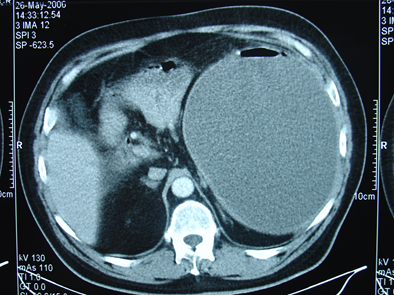

- Kontrastlı KT və ya MRT standart müayinədir, şişi və yayılma dərəcəsini müəyyənləşdirilməsində önəmlidir.

- Görüntüləmdə: erkən arterial fazada contrast tutan və venoz fazada yuyulan, MRT-də hipointens, ətraf toxumalara invaziv, böyüməyə meylli, baş nahiyyəsində yerləşərək xoledoxu və pankreatik axacağı genişləndirən (“iki axacaq simptomu”) törəmə

- Kontrastlı KT və ya MRT ilə pankreasda kütlə təyin İnsulinomalardan fərqli olaraq qlükaqonomalar böyük ölçülü olurlar və tapılması çətinlik törətmir. Adətən cisim və quyruq nahiyyəsində yerləşirlər.